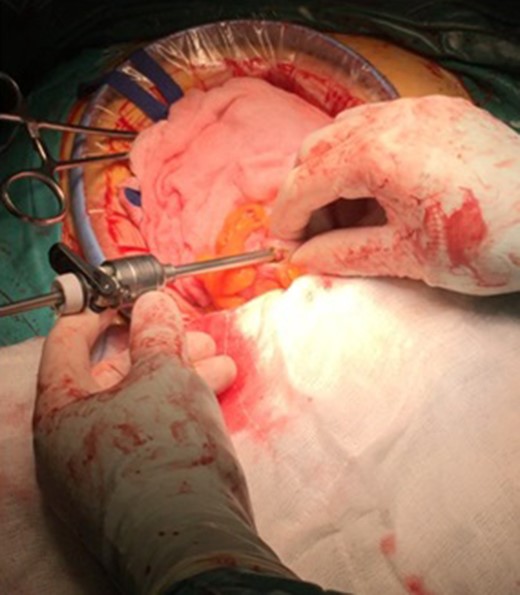

An isolation of the peritoneal cavity with compresses was initially performed. A cross-section of the peripheral truncation was performed on the colonic tape at the point where the ileocolonic anastomosis would be later created. A 10 mm laparoscopic port was inserted in the hole and CO2 insufflations started (Fig. 1). After bowel dilatation the camera was inserted through the laparoscopic port in the colon lumen. During the time the camera is intraluminal, water injection is provided, to avoid thermal injury of the mucosa. Overview of the lumen, until the splenic flexure bend and the beginning of the descending colon was performed. A hole was then applied to the colic tape at the lower third of the sigmoid (Fig. 2). Again, a 10 mm laparoscopic port was inserted and the laparoscopic camera was used to inspect the bowel lumen up to the splenic flexure. After the endoscopic inspection of the bowel has been completed, the laparoscopic ports were withdrawn (Fig. 3). The holes were converged with seromuscular stitches of the sigmoid and omentumplasty. A stapled side to side anastomosis was hen performed between terminal ileum and colon. The patient discharge hospital without any complication on the eighth postoperative day. The histopathology of the specimen shows low grade adenocarcinoma of the colon, pT4bN1b.

The insertion of the port at transverse colon and the isolated operation field with compresses.